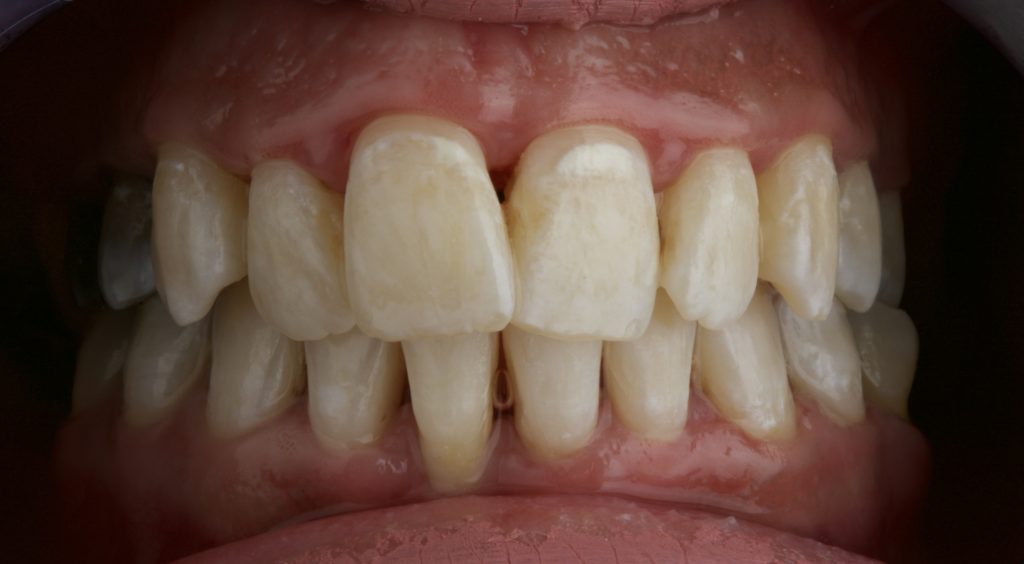

- Heavy calculus deposits on anterior and posterior teeth.

- Stage III periodontitis with gingival inflammation.

- Generalized extrinsic tooth staining.

- Significant improvement in gingival health after calculus removal.